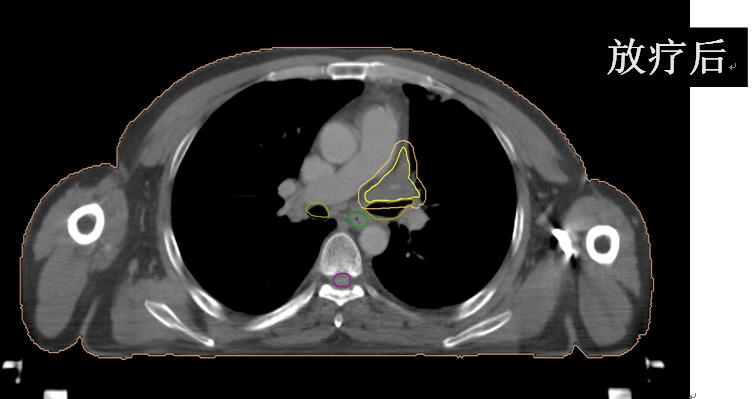

放疗后患者咳嗽、咳痰、左肩背部疼痛、痰中带血、胸闷、气短完全缓解;继续于外院行综合治疗并定期随访观察。

有图有真相:放疗效果显著!是不是疗效好就应该损伤重呢?肺损伤?